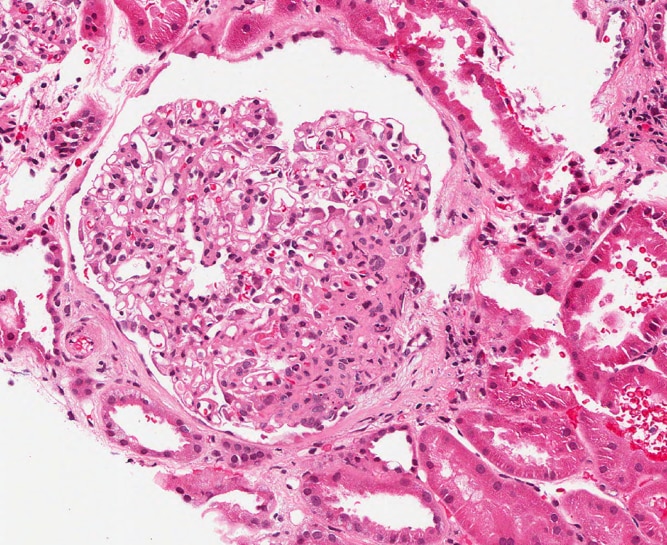

The Clinical Nephrology Section studies various kidney diseases, including membranous nephropathy and focal segmental glomerulosclerosis. The goal of our research is to better understand the evolution and outcomes of these kidney diseases and find treatments that may be more effective and less toxic.

Research Images